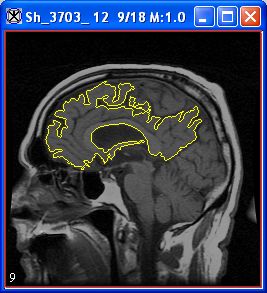

VOI > Evolve Boundary 2D > Active GVF. The Evolve Boundary dialog box uses a special type of active contours, or snakes to find the object boundaries. GVF or the gradient vector flow snake, which is used to calculate VOI boundaries, begins with the calculation of a GVF field of forces by applying generalized diffusion equations to both components of the gradient of an image edge map. Here, GVF fields, are dense vector fields derived from images by minimizing a certain energy functional in a variational framework. The minimization is achieved by solving a pair of decoupled linear partial differential equations that diffuses the gradient vectors of a gray-level or binary edge map computed from the image. See also Figure 3.

VOI > Evolve Boundary 2D > Spline active contour. This algorithm determines the structure's boundary less quickly than the Active Contour algorithm, however it is less sensitive to noise. This algorithm fits a spline to the data. When complete, the MIPAV-generated contour appears around the structure.

VOI > Evolve Boundary 2D > Spline GVF. This is the combination of the GVF force with the B-spline snake. B-spline snakes have several characteristics which make them well suitable for describing VOI boundary as well as snake evolution: the B-spline implicitly incorporates contour smoothness and avoids the ad hoc< tension and rigidity parameters of the traditional GVF snake and also fewer sample points are required to implement contour evolution for the B-spline.